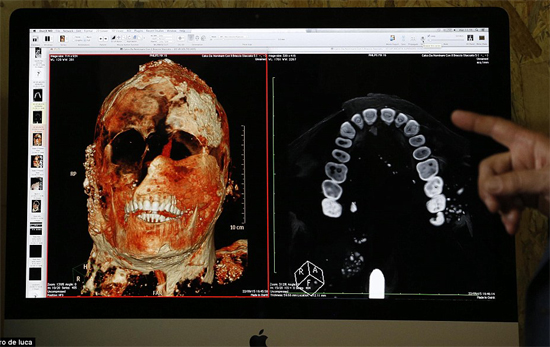

Estos son los primeros sorprendentes detalles que han sido comunicados el 27 de septiembre de 2015, producto de una investigación sin precedentes. Los investigadores han sometido a tomografías axiales computerizadas (TAC) cerca unos 30 cuerpos que fueron encontrados en las excavaciones de Pompeya, los cuales quedaron conservados en moldes de yeso con los que fueron tratados.

Los primeros resultados de estos exámenes que fueron comunicados en rueda de prensa han determinado que la mayoría de los habitantes de Pompeya tenían dientes sanos, gracias a una alimentación sana, con pocos azúcares. Aunque en algunas de las dentaduras se pueden observar imperfecciones que indican que el pompeyano utilizaba los dientes para romper o cortar. Por ejemplo, los primeros análisis en un hombre han revelado un problema en los huesos debido a la excesiva presencia de flúor en las faldas acuíferas vesubianas.

La maquinaria utilizada es una moderna TAC de 16 cortes capaz de hacer un examen de todo el cuerpo en 100 segundos, explican los investigadores. El gran problema es "la densidad del yeso utilizado, pues es muy parecida a la densidad de los huesos y por ello ha sido necesario recurrir a la alta tecnología de una TAC de 16 cortes", explicó hoy el superintendente de Bienes Culturales de Pompeya, Massimo Osanna.